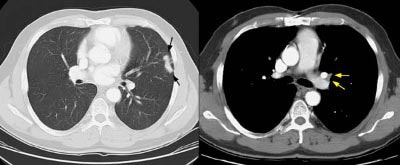

Example 1: This is an example of an N1 node in a patient with a lingular adenocarcinoma (left image). Although not pathologic by short axis size criteria, the lymphatic tissue in the left hilum has a convex border with the adjacent lung (white arrows). This node contained adenocarcinoma at histopathologic analysis. Some authors advocate using the presence of a convex margin of the interstitium with the lung parenchyma to indicate pathologic adenopathy to improve the sensitivity of CT for detecting hilar metastases [36].

Example 2: This patient is an example of a false negative CT for hilar nodal metastases even when applying the suggested new criterion. The patient had a peripheral adenocarcinoma in the left upper lobe (black arrows). The left hilar node (yellow arrows) is not pathologic by size criteria, nor does it exhibit a convex margin with the adjacent lung parenchyma. This is a normal node by CT, however, at histopathologic analysis the node was positive for malignant cells.